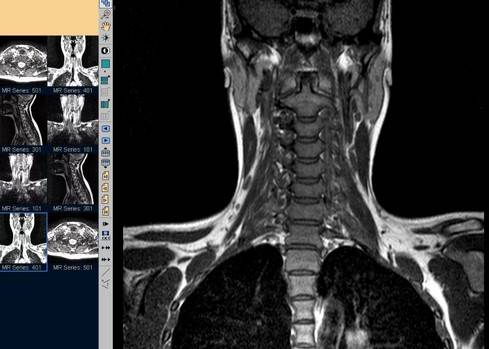

Магнитно-резонансное сканирование шейного отдела позвоночника